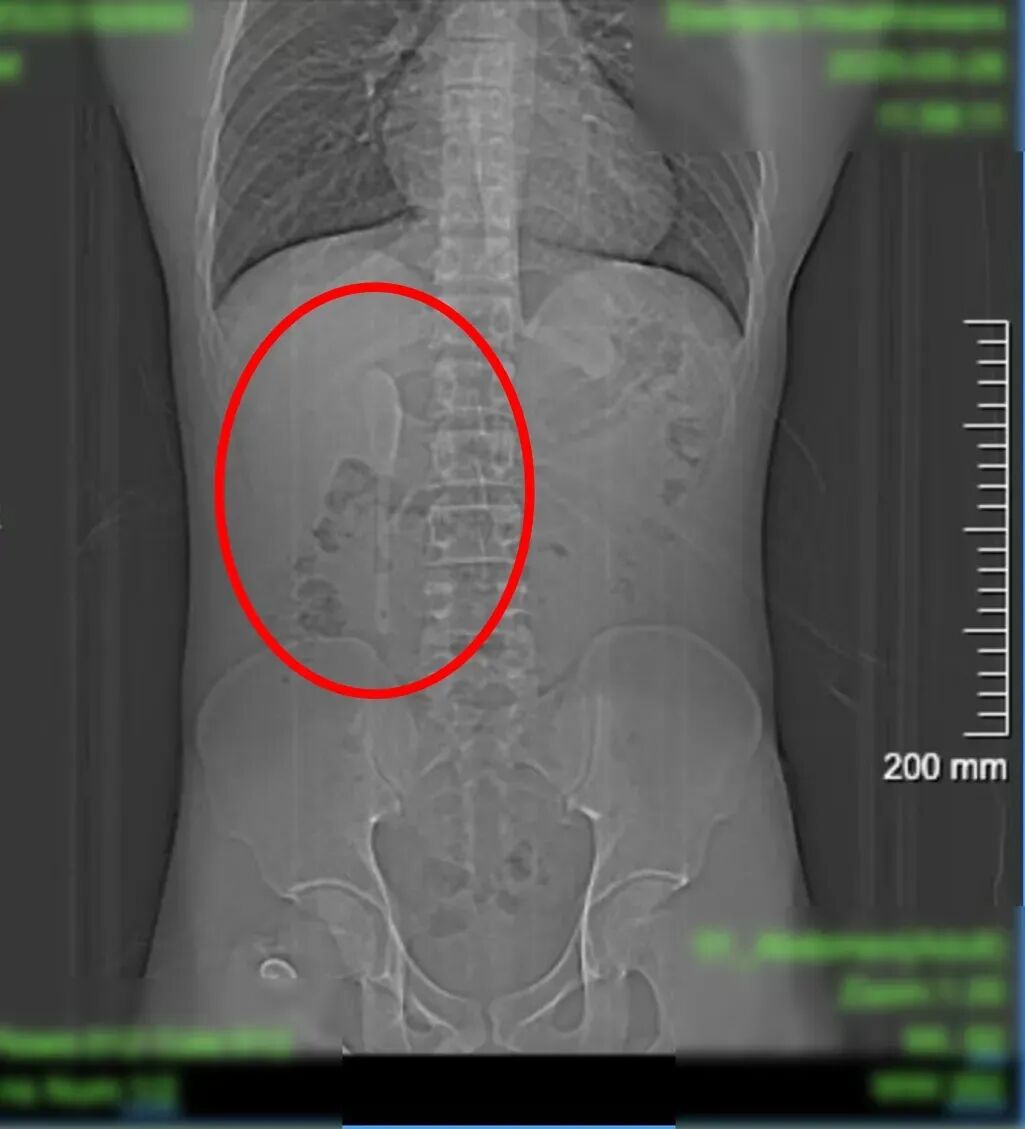

CT显示这支近15厘米长勺状物体

严丝合缝地横亘于

十二指肠球部与降部交界的生理狭窄处

稍有不慎即可能刺穿肠壁

引发腹膜炎或大出血

这支被遗忘的勺子,历经6个月胃肠蠕动,最终精准卡进十二指肠球部与降部交界处。此处腔隙狭窄且肠壁极为菲薄,异物极易嵌顿,稍有不慎容易造成穿孔。中山医院内镜中心主任周平红教授解释:“勺子陶瓷质地光滑细长,十二指肠球降交界又是人体上消化道的生理狭窄处,内镜下取出难度极大。若失败,只能开腹手术。”